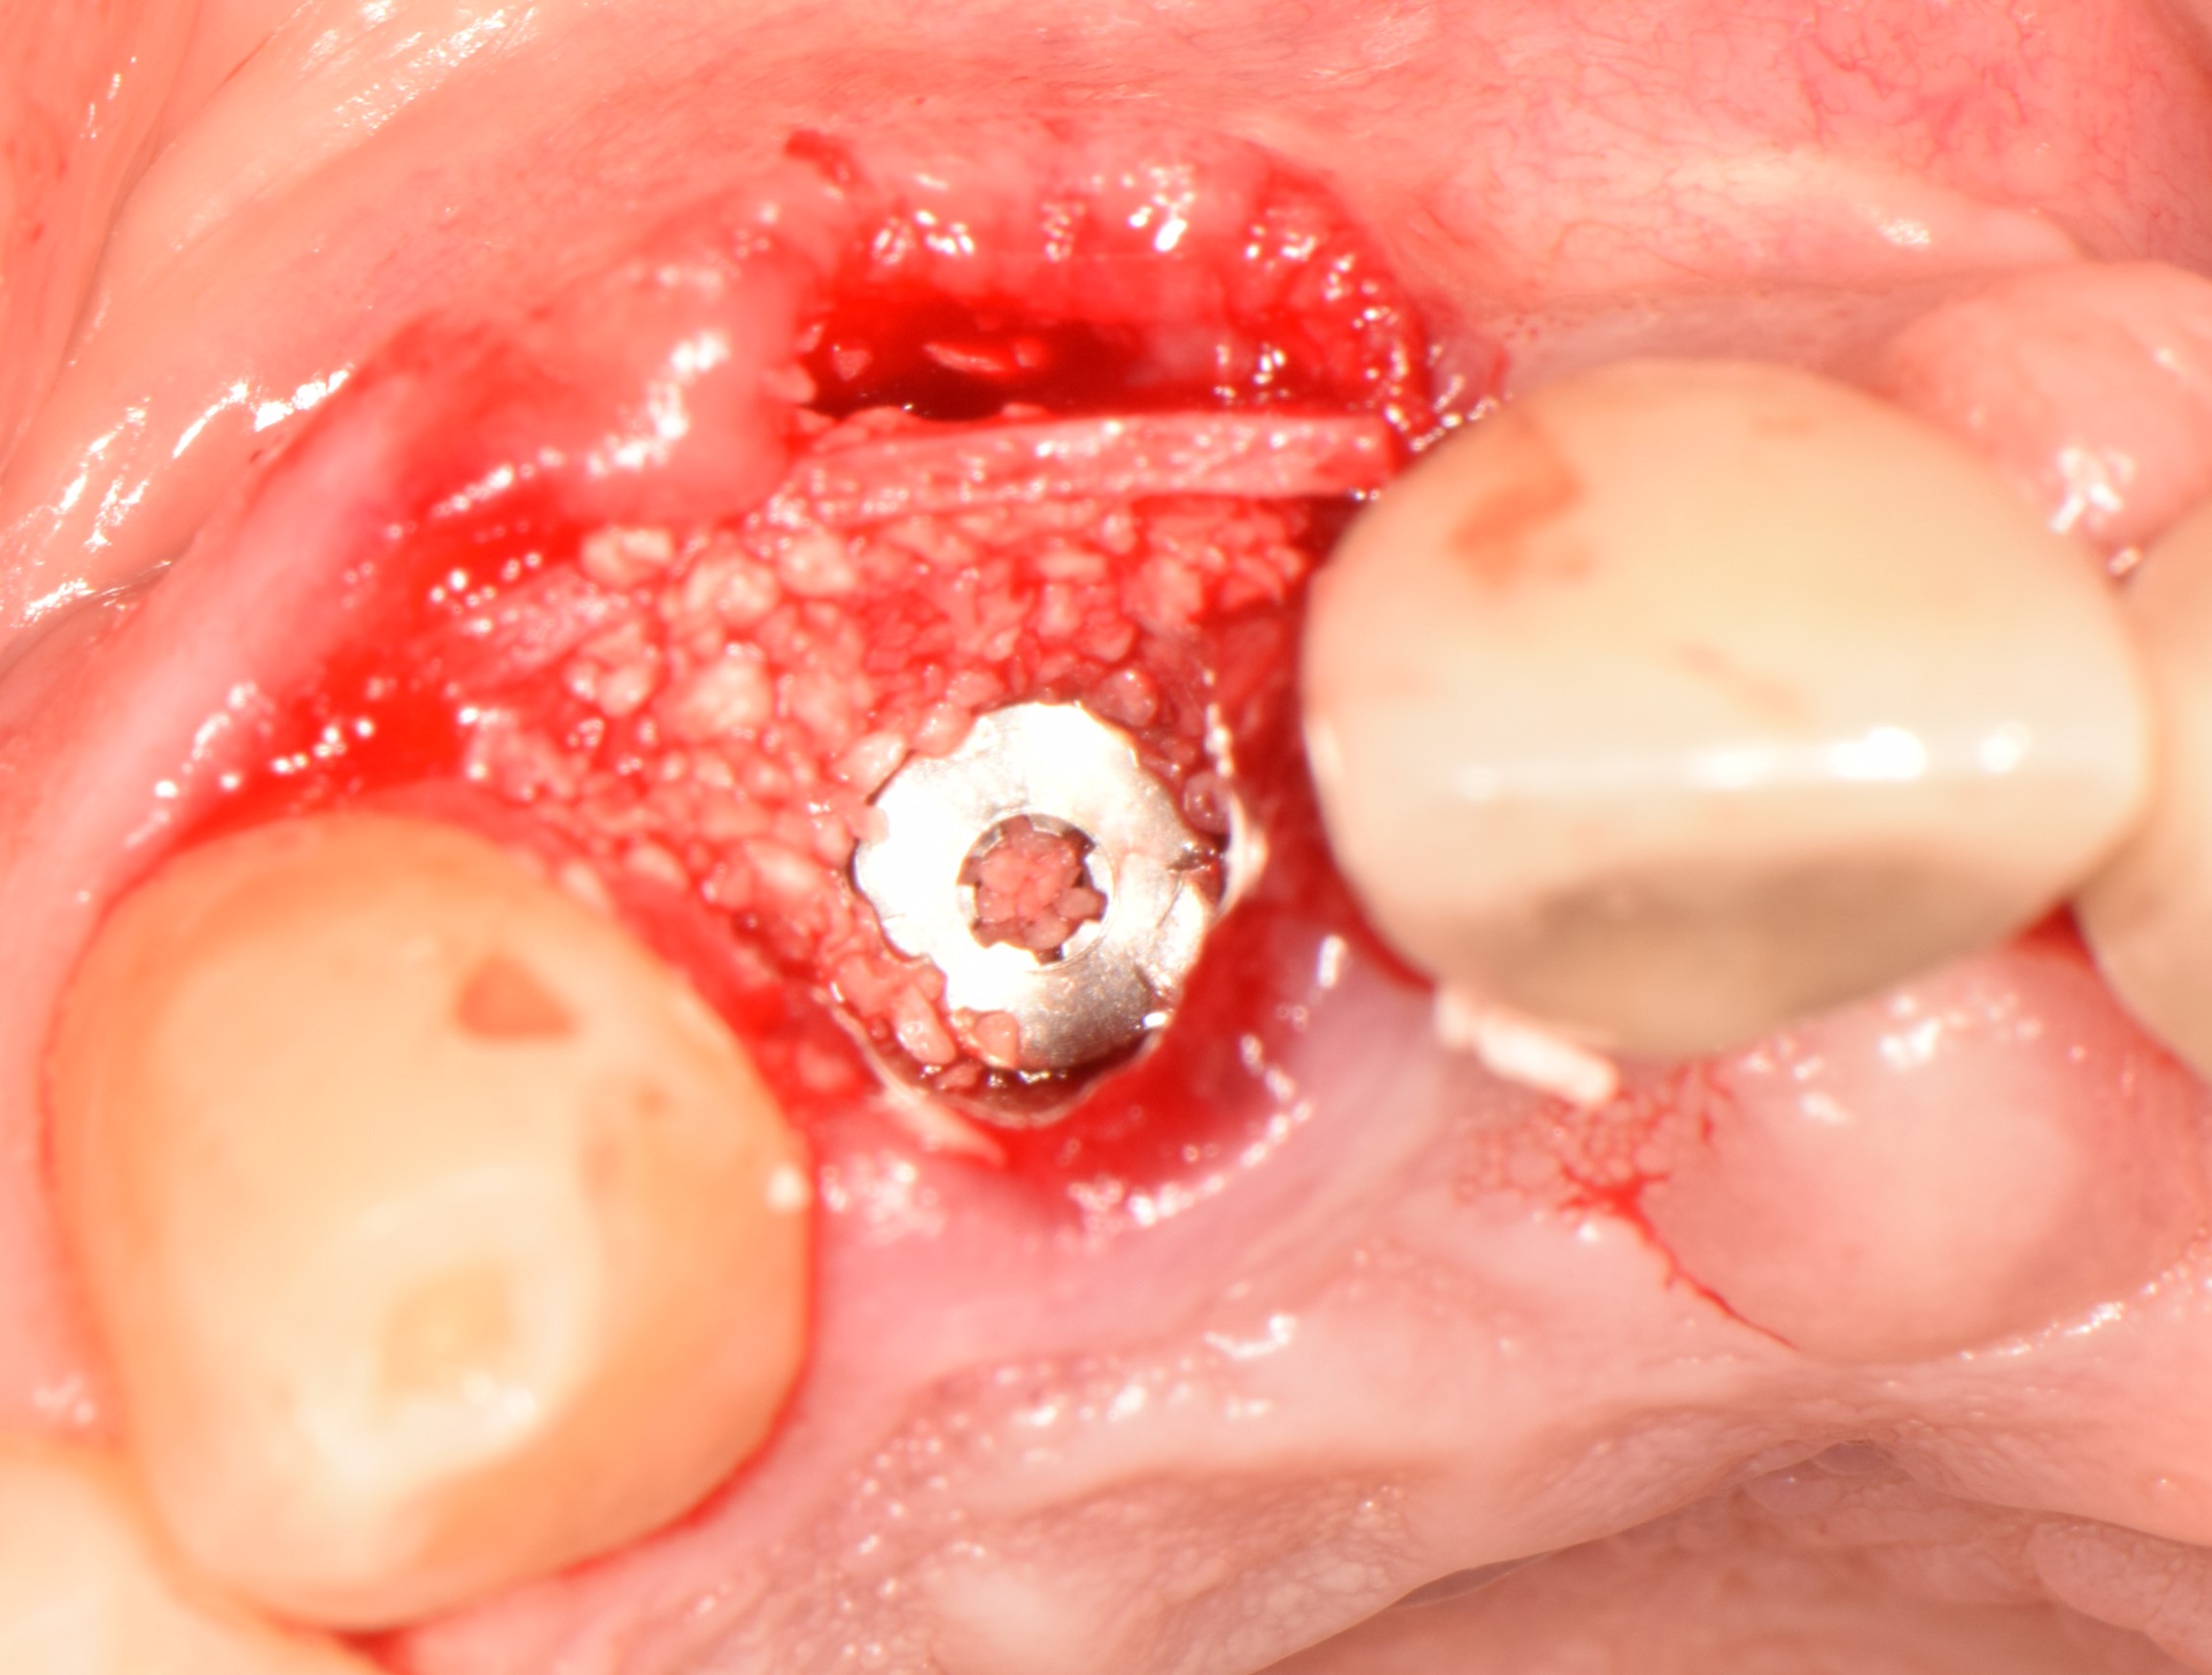

Regeneración ósea guiada (ROG) utilizando injertos óseos de origen equino junto con una lámina cortical.

El caso clínico que nos ocupa se refiere a una paciente de 62 años que acudió al dentista por la descementación del elemento dental 12. El examen radiográfico mostró una fractura radicular que hacía irrecuperable el elemento. Se extrajo la raíz restante y se elevó un pequeño colgajo y se realizó una incisión fijada con pegamento de fibrina. La cavidad formada entre la lámina y el implante se rellenó con injerto óseo granular conservado con colágeno, estabilizado con pegamento de fibrina. La operación se completó suturando las papilas y aplicando un tornillo de cicatrización. A los 9 meses de la regeneración, se realizó una radiografía de control que mostró una excelente integración del injerto granular y el mantenimiento de los picos óseos mesial y distal.

PRODUCTOS UTILIZADOS: Osteoxenon, Granules, Mix, Flex Cortical Sheet